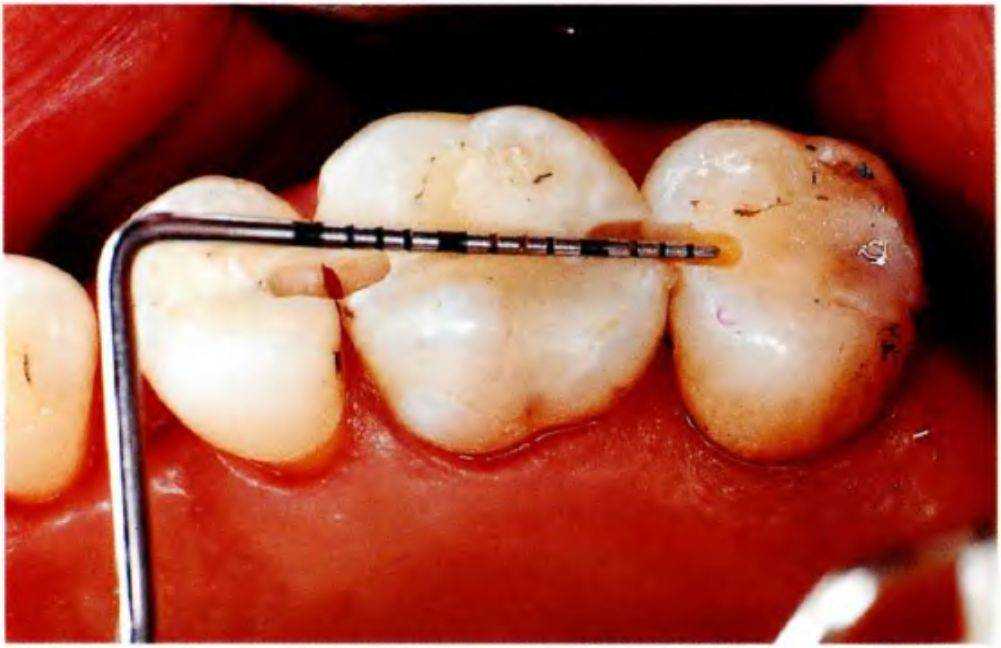

Затем с помощью лампы тщательно полимеризуют шину с противоположных сторон, начиная с латеральной (через эмаль) (рис. 4-21). При необходимости шину препарируют и полируют. После этого проверяют окклюзию, обучают пациента правильной чистке межзубных пространств и проверяют его способность осуществлять самостоятельную гигиену полости рта (рис. 4-2т и 4-2п).